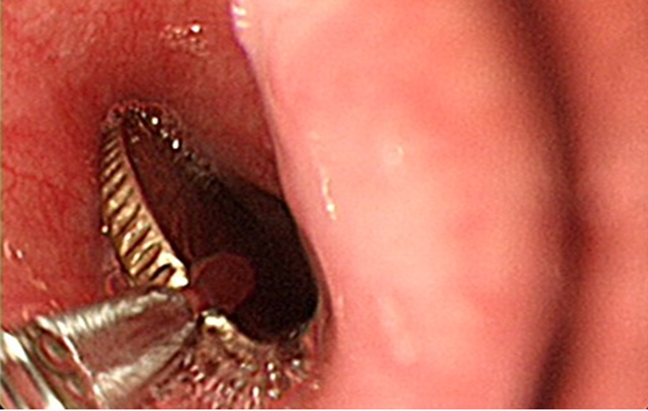

醫師指出,「硬幣」位居嬰幼兒誤吞異物之冠,其他常見的還有小玩具、小飾品、鈕扣電池及磁鐵等。 圖/萬芳醫院提供

劉喆瑩說,所幸,這枚硬幣卡得不深,整個執行胃鏡的過程不到五分鐘就取出了。主要是嬰幼兒執行胃鏡取異物通,常需要進行全身麻醉以及適當設備,前置作業往往最耗時。陳小妹妹最後在全身麻醉的狀況下,順利以胃鏡取出硬幣,留院觀察無後遺症,也順利返家,結束了這將近半天的「驚魂記」。